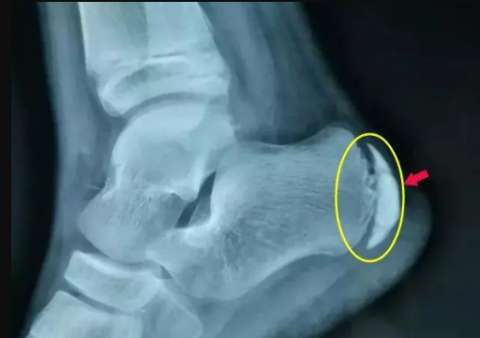

孩子这个地方疼,家长千万别大意

当孩子和你说脚后跟疼的时候,你会不会条件反射的说:“小孩子怎么会脚后跟疼?” 当孩子跑步、上楼梯、或脚后跟受到压迫疼痛加剧时,你有没有足够的重视? 如果...